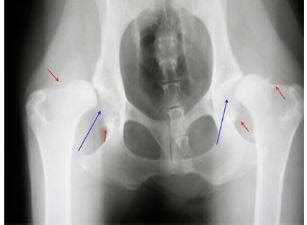

- Dysplázia bedrového kĺbu u psov (DBK): Je geneticky podmienená porucha vývoja kĺbov. Vyskytuje sa predovšetkým u stredne veľkých a veľkých plemien psov. Príčinou dysplázie je tzv. voľný bedrový kĺb, kedy hlavica stehennej kosti nie je správne umiestnená v kĺbovej jamke, ale sa voľne pohybuje.

Ide o skupinu zápalových ochorení kĺbov patriace medzi takzvané degeneratívne reumatoidné ochorenia. Často sa môžete stretnúť aj s názvom osteoartróza. Dochádza pri nich k úbytku kĺbovej chrupavky a neskôr ochorenie zasahuje aj okolité tkanivá. Osteoartróza je chronické a progresívne ochorenie, pri ktorom, ak nastanú zmeny, sú nezvratné. Rozlišujeme primárne a sekundárne. Vo svete zvierat je primárna OA skôr vzácna a vzniká bez predchádzajúcej traumy či iného poškodenia. Tá sekundárna vzniká vplyvom degeneratívnych zmien na kĺboch, ako sme už vyššie spomenuli. Ďalej tiež vzniká veľmi často po úrazoch a zápaloch v rámci pohybového aparátu. Spôsobuje bolesť. Nepríjemné bolestivé stavy sú spôsobené deštrukciou chrupavky a vznikom následného zápalu okolitých mäkkých tkanív. Kĺbová chrupavka slúži ako tlmič nárazov medzi kosťami. Za normálnych fyziologických podmienok je jej povrch hladký a kĺzavý, čo umožňuje plynulý a nebolestivý pohyb v kĺbe. Pri poškodení chrupavky je narušený ochranný vankúš a kĺby podliehajú opotrebovaniu. V snahe spomaliť ďalšiu deštrukciu vytvára telo nové kostné výrastky nazývané osteofyty alebo kostné ostrohy, ktoré sú už viditeľné na zobrazovacích technikách, ako je RTG vyšetrenie.